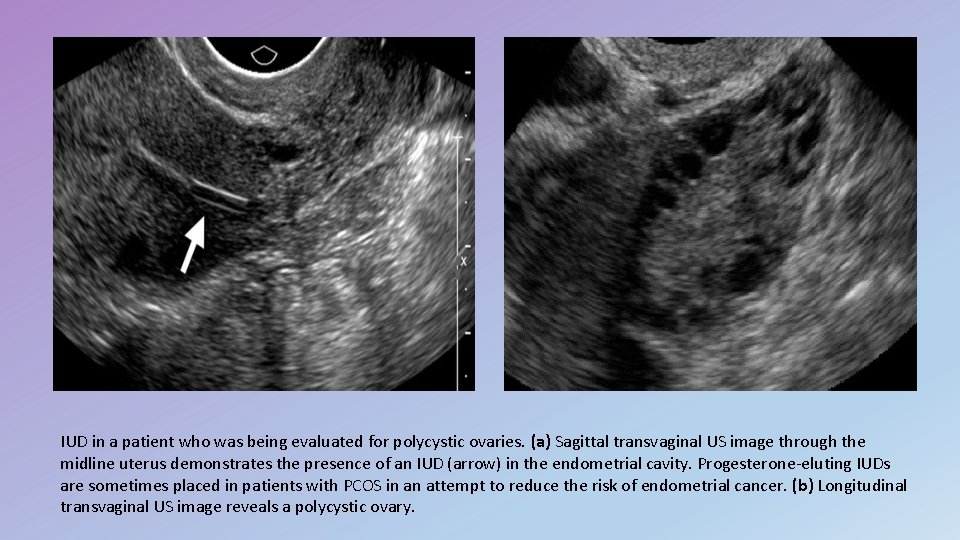

IUD in a patient who was being evaluated for polycystic ovaries. (a) Sagittal transvaginal US image through the midline uterus demonstrates the presence of an IUD (arrow) in the endometrial cavity. Progesterone-eluting IUDs are sometimes placed in patients with PCOS in an attempt to reduce the risk of endometrial cancer. (b) Longitudinal transvaginal US image reveals a polycystic ovary.